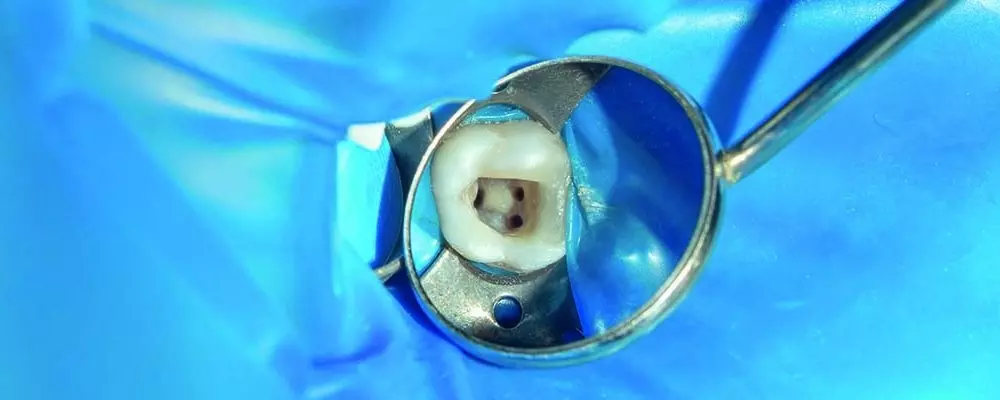

PRACTISE & CASES

- Maciej Mikołajczyk

- 31 stycznia 2020